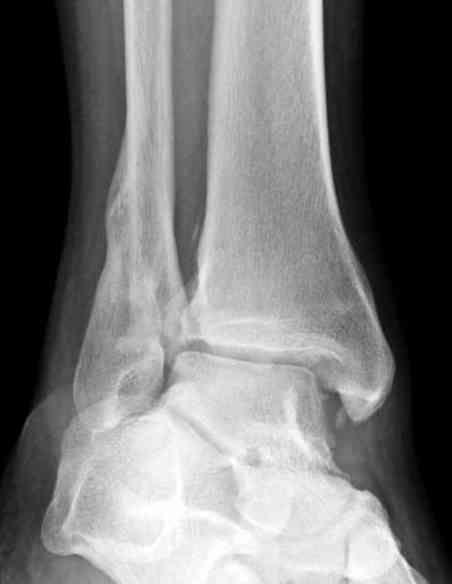

Согласен, на предоставленных рентгенограммах все основания для проведения открытого остеосинтеза.

Здесь представлено решение похожей проблемы. Больной в течение года лечился консервативными мерами, и боли в голеностопе были основным показанием к операции.

Проведена обычная стандартная процедура по исправлению неудовлетворительного состояния голеностопного сустава, где кроме удлинения малоберцовой с применением compression tension device за проксимальный конец пластины, проведено замещение трикортикальным графтом из крыла, освобождение синдесмоза и медиальной щели от

фибротических масс с фиксацией.